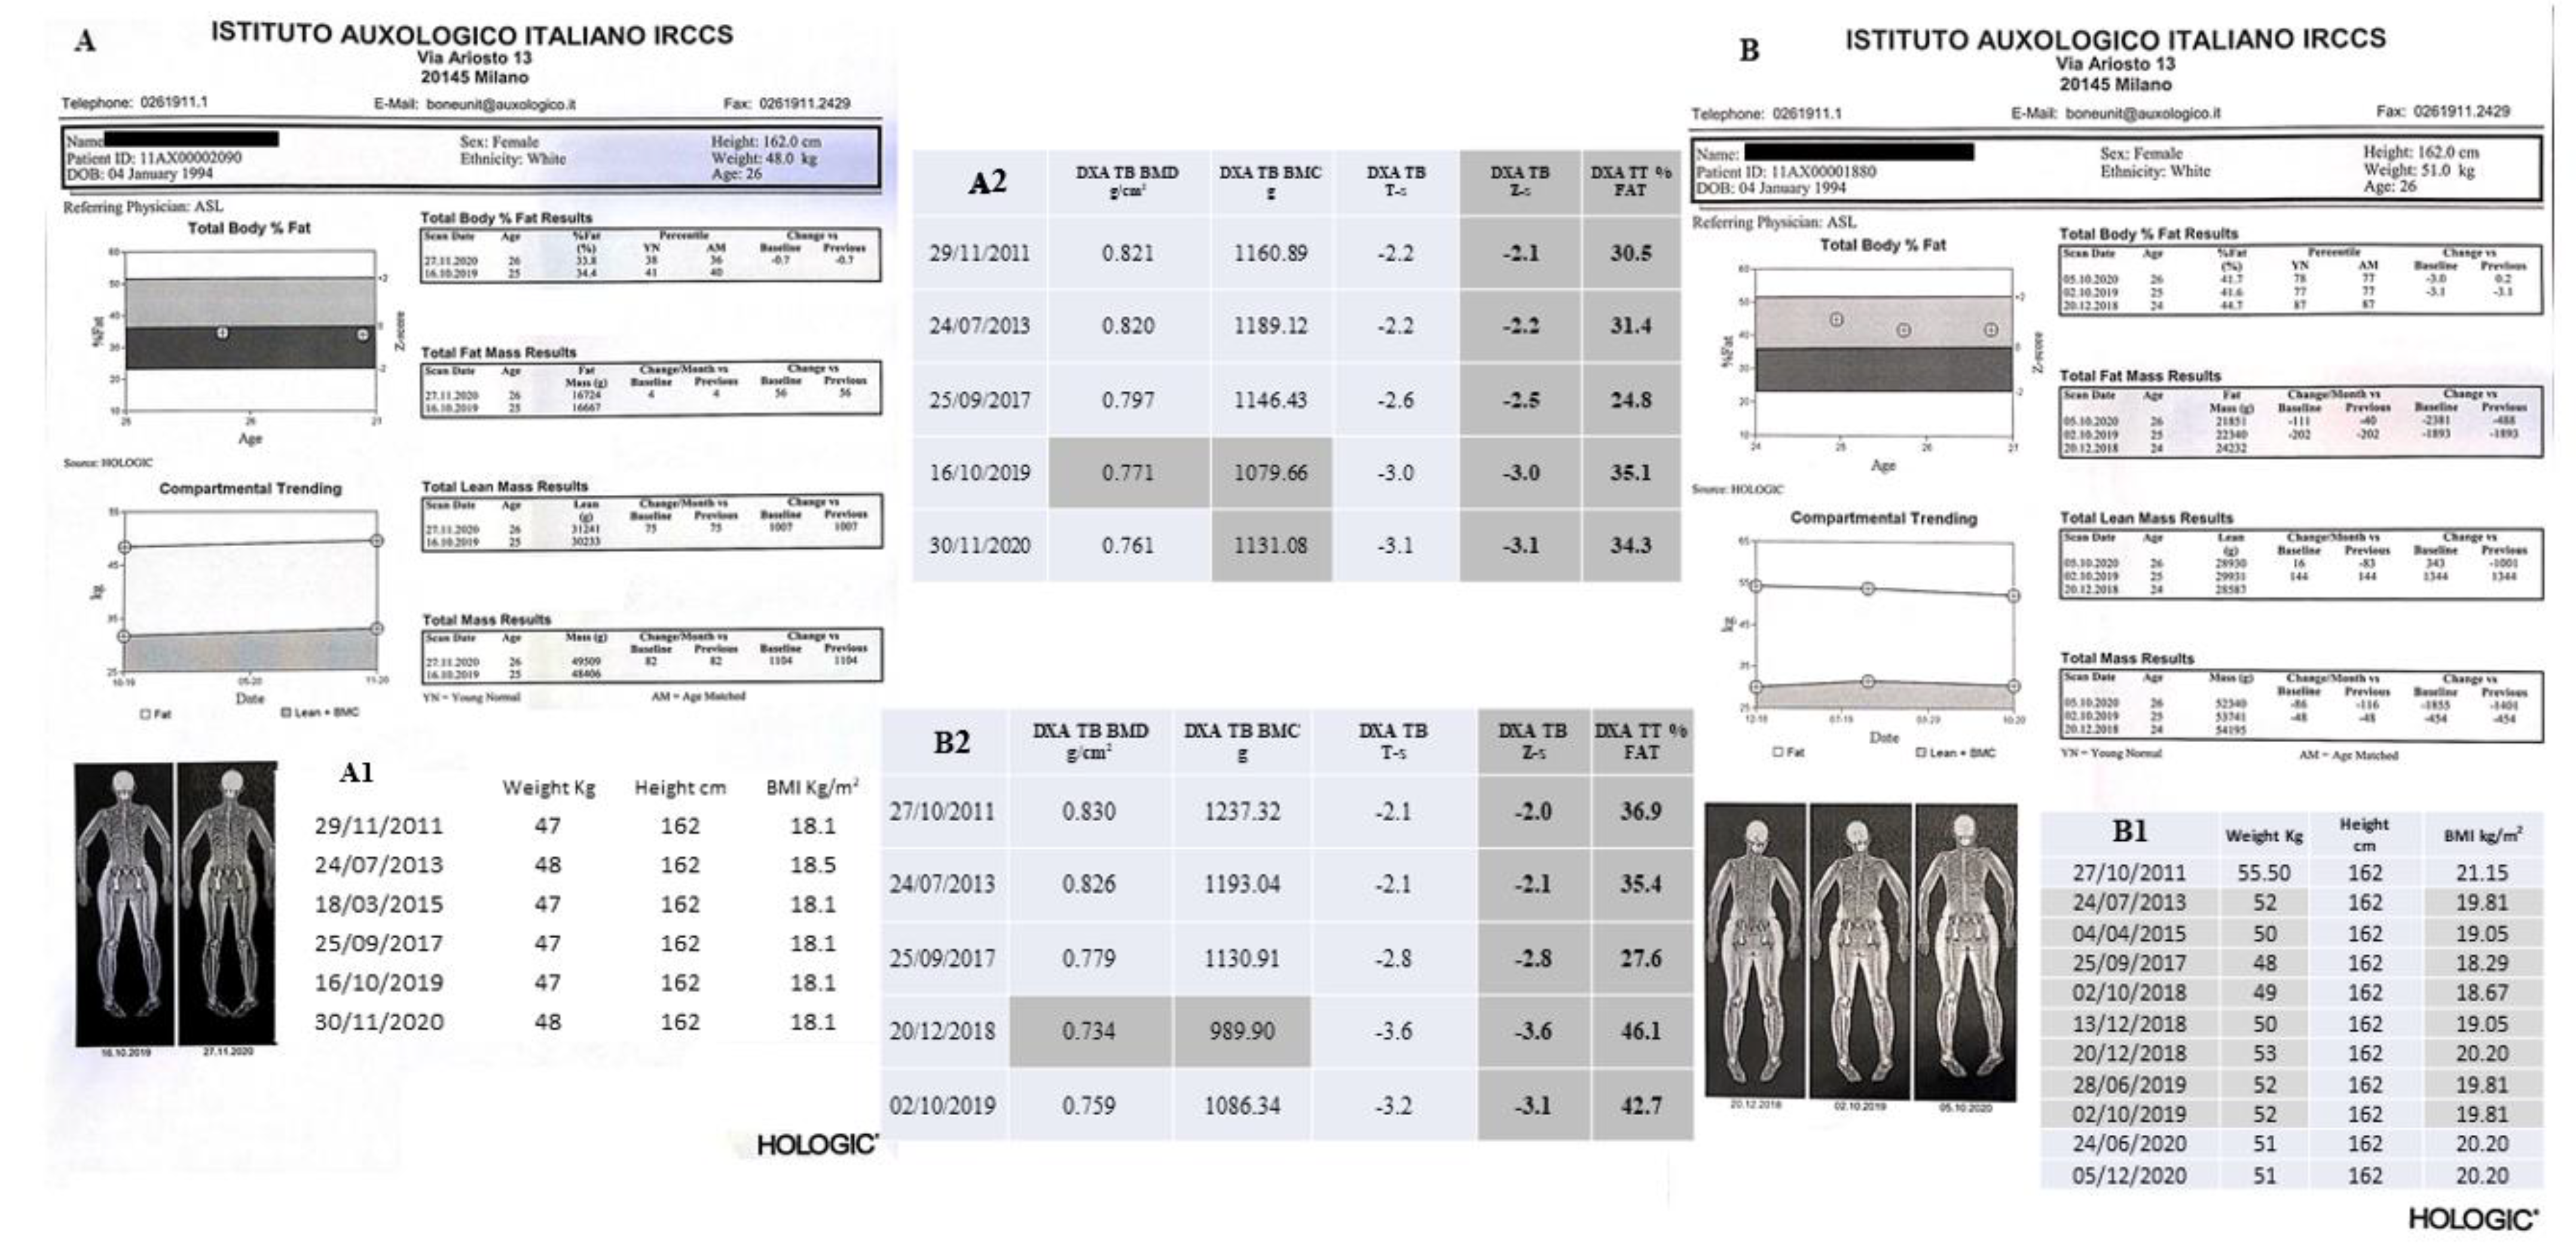

3.1. Bone Phenotyping

3.1.1. Dual Energy X-ray Absorptiometry (DXA)

4.1. DXA Scans

4.1.1. II-1 Tw1

4.1.2. II-2 Tw2